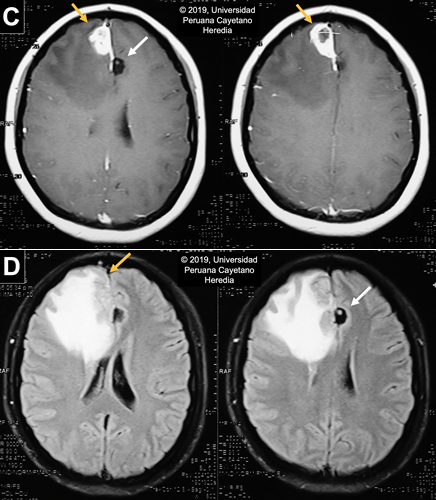

Imaging studies: Normal CXR. Non-contrast head CT scan reveals a hypodense lesion in the right frontal lobe with extensive perilesional edema that produces a midline shift that compresses the right lateral ventricle. No apparent hydrocephalus. Two cystic lesions are present in the left parietal lobe and in the parasagittal frontal lobe. Multiple thick calcifications are found in the parenchyma (Image A). The MRI finds the same parenchymal fluid-filled cystic lesions with a punctiform structure inside. In the contrast T1 view, there is a heterogeneous hyperintense area, with a hypointense center, near the meninges in the right frontal lobe associated with moderate edema, suggestive of a granulomatous process (Image B).

![]() Discussion: Serum Western Blot for Taenia solium was positive (Reactive in 5 bands: 42kd, 35kd, 31kd, 24kd, 14kd). Stool O & P testing was negative. Upper abdominal US was unremarkable. Neurocysticercosis (NCC) is a disease caused by the larval stage of the pork tapeworm Taenia solium and contributes to approximately 30% of the burden of seizures in endemic areas in the developing world (PLoS Negl Trop Dis. 2010 2;4(11):e870), which includes the most Latin American countries, Sub-Saharan Africa, Southeast Asia, China and the Indian subcontinent.(PLoS Negl Trop Dis. 2012 29;6(5):e1500). In the United States, it is estimated that there are 2,361 inpatient cases per year with an economic impact of US $908,238,000 per year and US $50,000 per hospitalization (Emerg Infect Dis. 2015;21(6):969–76; Am J Trop Med Hyg. 2015;92(2):354–9). Humans become infected by accidental ingestion of eggs from feces; the eggs then develop into a larval stage (cysticercus) in several tissues with a marked preference for the CNS and muscles. Infection and development into the adult stage (intestinal tapeworm), occurs when cysts in undercooked pork meat are ingested. The adult tapeworm elongates forming new segments called proglottids, which eventually detach and are shed in stools. These contain thousands of eggs that have the potential to infect new hosts or continue to infect their present host. The spectrum of clinical manifestations is based on the acute or long-term effect of the inflammatory reaction and mass effect. These vary according to the staging and location of the cysts. Parenchymal cysts could present with headaches or seizures, while intraventricular cysts may obstruct CSF flow and cause acute obstructive hydrocephalus (Radiology of Infectious Diseases. 2015 M;1(2):94–102). Active CNS lesions can be identified by CT or MRI; the former excels at identifying calcifications while the latter distinguishes smaller lesions and scolices and provides greater insight for evaluating degenerative changes and edema (Neuroimaging Clin N Am. 2012;22(4):659–76). Neuroimaging findings vary according to the involution of the cysts; our patient presents with lesions on different stages. On CT scan, live vesicular cysts are well-defined, isodense fluid-filled round lesions without surrounding inflammation that does not enhance after contrast administration: scolex may be seen within the cyst as a hyperintense bud, the “hole-with-dot” sign [White arrow in Image C and D]. As the immune system recognizes the cyst, the lesion begins to degenerate into the colloidal stage [Yellow arrows in Image C and D], which presents with poorly-defined borders and extensive perilesional edema seen as a ring-enhancement lesion. No scolices are observed during this stage. The granular stage presents as an entirely collapsed cysts by the host’s immune response. It is also described as small annular or nodular lesions that enhance after contrast administration. The last stage of the lesion, the calcified cysticerci [Image A], is a non-enhancing hyperdense nodule on the CT scan (Radiology of Infectious Diseases. 2015;1(2):94–102; Infect Dis Clin North Am. 2019;33(1):153–68; Neurol Clin. 2018;36(4):851–64). Although most of the images are compatible with NCC, the lesion on the right frontal lobe is atypical and the differential diagnosis is extensive including brain abscesses, tuberculosis, toxoplasmosis, primary brain tumors (meningioma) or metastases. However, due to the presence of other pathognomonic lesions and a positive Western Blot result, we can deduct that this is a cysticercus in a degenerative stage. Anticonvulsant administration is the first step in the management of NCC patients presenting with seizures. Pain management should also be a priority. In the case of raised intracranial pressure options include the use of steroids, acetazolamide, mannitol or surgery, usually shunt placement if there is hydrocephalus (Neurol Clin. 2018;36(4):851–64). Antiparasitic regimens of choice include albendazole alone or combined with praziquantel. Corticosteroids must be given to these patients as there is an initial inflammatory response from the death of the parasites. Additionally, prior to initiation of therapy, ophthalmologic examination should rule out the presence of cysticerci in the eye since degeneration of the cyst can impair vision. The inflammatory response varies between patients and it may be severe when there are multiple or large lesions. This is why starting therapy is not an emergency; each case must be evaluated and individualized accordingly. Our patient was managed with mannitol and acetaminophen to alleviate symptoms while MRI and Western Blot were obtained. Due to the current extensive inflammatory process caused by the lesion’s degeneration, antiparasitic treatment was delayed and the patient was discharged to be closely follow at our outpatient service. The neurologists following her case have requested an imaging follow-up in a month to reassess the appropriate time of starting therapy, which will depend on the decrease of the current inflammatory reaction in the right frontal lobe. Prevention of transmission of eggs between humans includes community awareness programs, good personal hygiene (especially among cooks and servers in the food industry), treatment for tapeworm carriers and administration of anthelmintic chemotherapy in pigs. Our patient was not aware of any household contact with T. solium infection so it’s possible that transmission may have occurred due to her eating habits and the poor hygiene standards of street food vendors. A study in a highly endemic region in Northern Peru tested several strategies for T. solium control that involved human and pig hosts. Results were promising as there was a clear decrease in the number of pigs infected among 107 rural villages (N Engl J Med. 2016;374(24):2335–44). The World Health Organization (WHO) identifies neurocysticercosis as a neglected tropical disease and has prioritized Taenia solium as the focus for new control initiatives. |